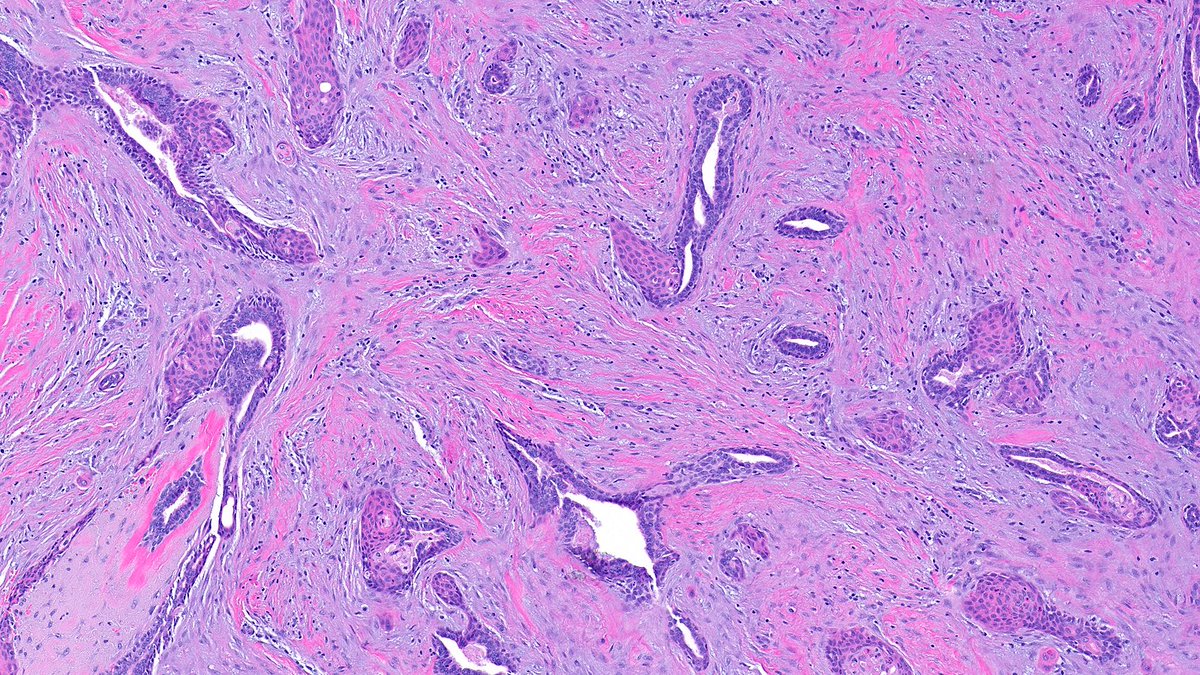

What’s the diagnosis of this papillary breast lesion? 🔬 Cast your vote below 👇 Answer revealed Monday! #PathX #PathTwitter #breastpath #PathQuiz

Delighted to share our latest article, "Challenges in papillary tumors of breast", published with my wonderful colleague @RazaHoda in @Human_Pathology! It's always a joy working together. Check it out here sciencedirect.com/science/articl…